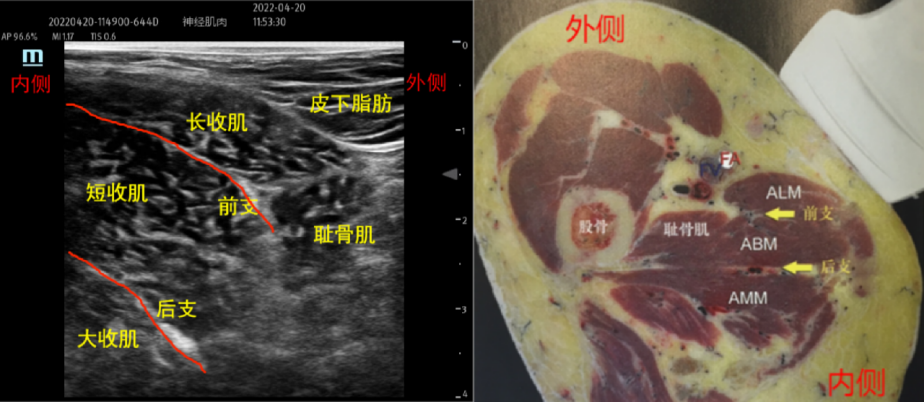

闭孔神经:闭孔神经起自腰丛,源于L2-L4脊神经前支。起自腰大肌内侧,在盆腔内穿出腰大肌,后沿着闭孔内肌下降,伴随闭孔动静脉出闭孔,分为前后两支,前支走行于耻骨肌、长收肌、短收肌间、闭孔外肌前方。后支走行于短收肌后方和大收肌之间的前方。

扫查方法:将探头平行于腹股沟韧带置于其下方,斜轴位由外侧→内侧探查,先找到股动脉,在股动脉内侧即为耻骨肌,继续向内侧移动,可见与耻骨肌内侧相邻的三层肌肉结构,由浅入深依次是长收肌→短收肌→大收肌。闭孔神经前支在长收肌和短收肌之间,后支在短收肌和大收肌之间。

穿刺方法:平面内法,大腿外侧进针,局麻药注射于长收肌和短收肌之间和短收肌和大收肌之间。

药物用量:0.33%-0.5%罗哌卡因前支和后支各5-10ml。